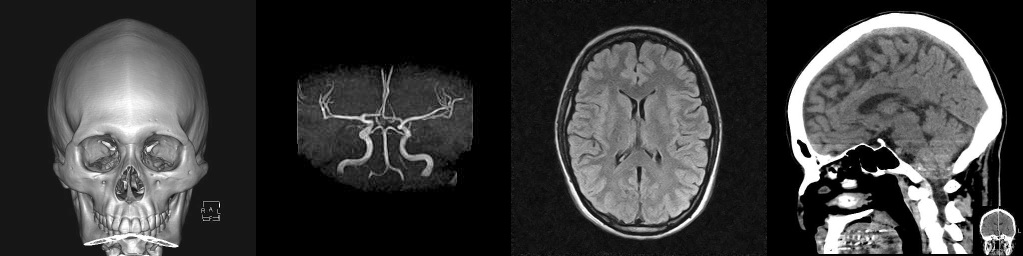

脳神経外科では、脳や脊髄神経を専門に診断・治療を行う診療科です。当科では、頭痛、脳卒中などの脳血管障害、頭部外傷、脳腫瘍などを対象に、診察・検査・治療を行っております。

また、当院ではオープン型MRIを設置しております。閉所が苦手な方(閉所恐怖症)でも安心して検査を受けていただける環境を整えており、検査中に付き添いの方がMRI室内に同席することも可能です。